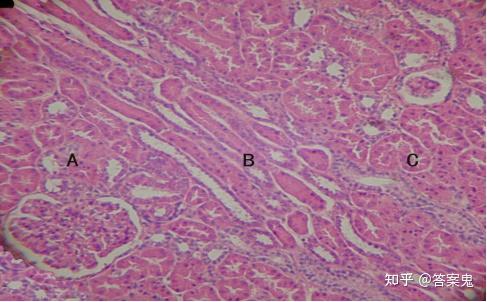

图15-1肾皮质(肾 he染色10×10) 图示肾皮质的皮质迷路(a,c)及中间的

皮质迷路和肾柱 b.髓放线和肾锥体 c.皮质浅部 d.